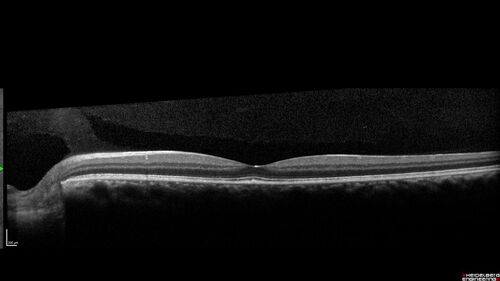

Syphilitic Chorioretinitis - 2 month post-treatment

41 year old man with vision loss for five days left eye. VA 20/32, 20/200

Syphilitic Chorioretinitis Both Eyes